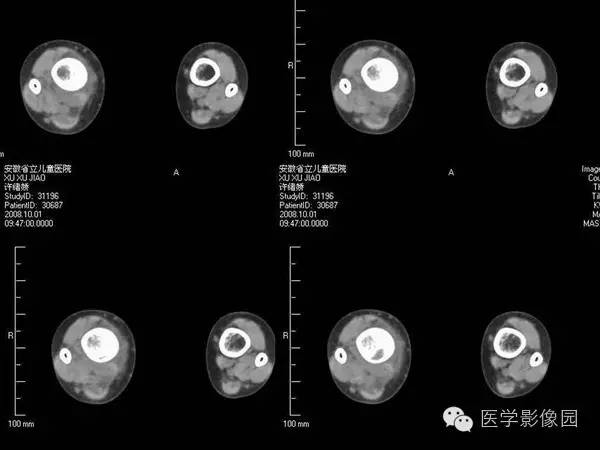

【病例】浆细胞性骨髓炎1例X线及CT影像表现